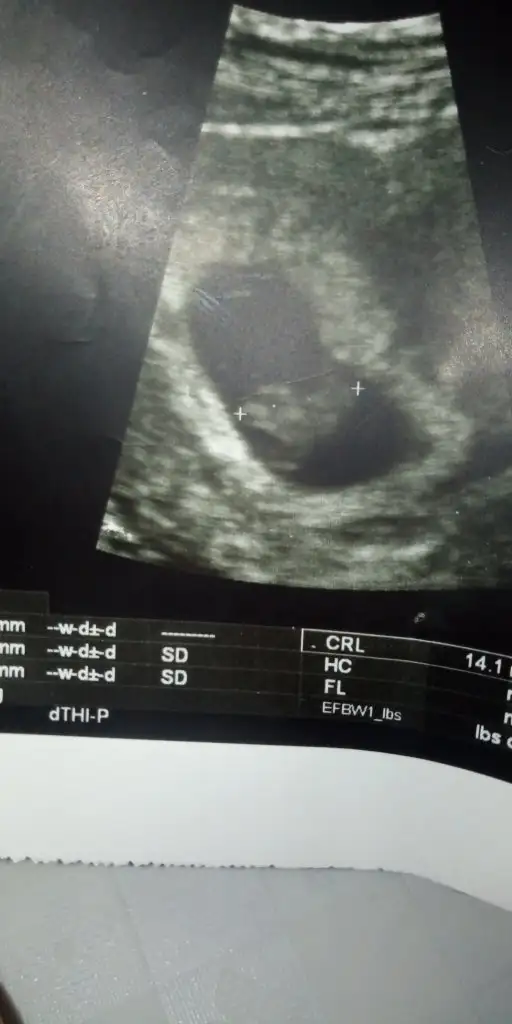

Karındansa Erkek vajinalsa kız buna göre 11 yada 12 hafta usg de nub teorisinde fazla yanılma olmuyorEki Görüntüle 2295192 merhabalar kızlar bana da yorumda bulunabilir misiniz karından usg 6 haftalık

Karındansa kız vajinalsa erkek tabi 11 yada 12 hafta usg paylaşın kese konumu tutmayada bilirEki Görüntüle 2295704

Buna göre kız 11 yada 12 hafta usg paylaşın kese konumu tutmayabilirmi?